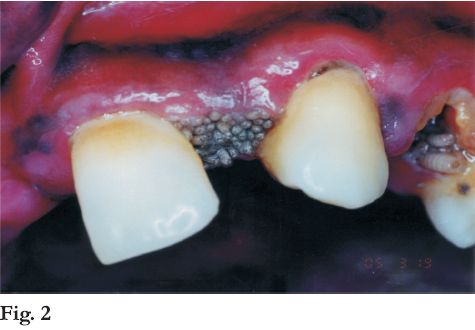

A nivel del maxilar presentaba edentación parcial anterior y restos radiculares de 2.3 y 2.4 rodeados por una encía edematizada y cubiertos por múltiples larvas de color blanco grisáceo, de cuerpo segmentado y 6 mm. de longitud promedio. Las mismas presentaban movilidad ocultándose frente a la luz del foco (Fotos 1, 2 y 3).

En la mandíbula, se observaron restos radiculares en la región correspondiente a molares y premolares, encontrándose también larvas en el lado derecho.

Desde el punto de vista clínico se diagnosticó miasis oral. Para conocer la extensión de la lesión se realizó una OPT descartando afectación ósea, nasal y de senos maxilares.

El tratamiento inmediato consistió en la eliminación con pinzas de la totalidad de las larvas en ambos maxilares (80 en total) y el lavado de la zona con solución de hipoclorito de sodio al 5%. Las larvas se conservaron en solución de formaldehído al 10% para su posterior clasificación.

En el primer caso, las larvas mostraban la morfología característica de la familia de las Calliphoridae. Son de tamaño variable y de cuerpo segmentado como gusanos blancos elongados y blandos.